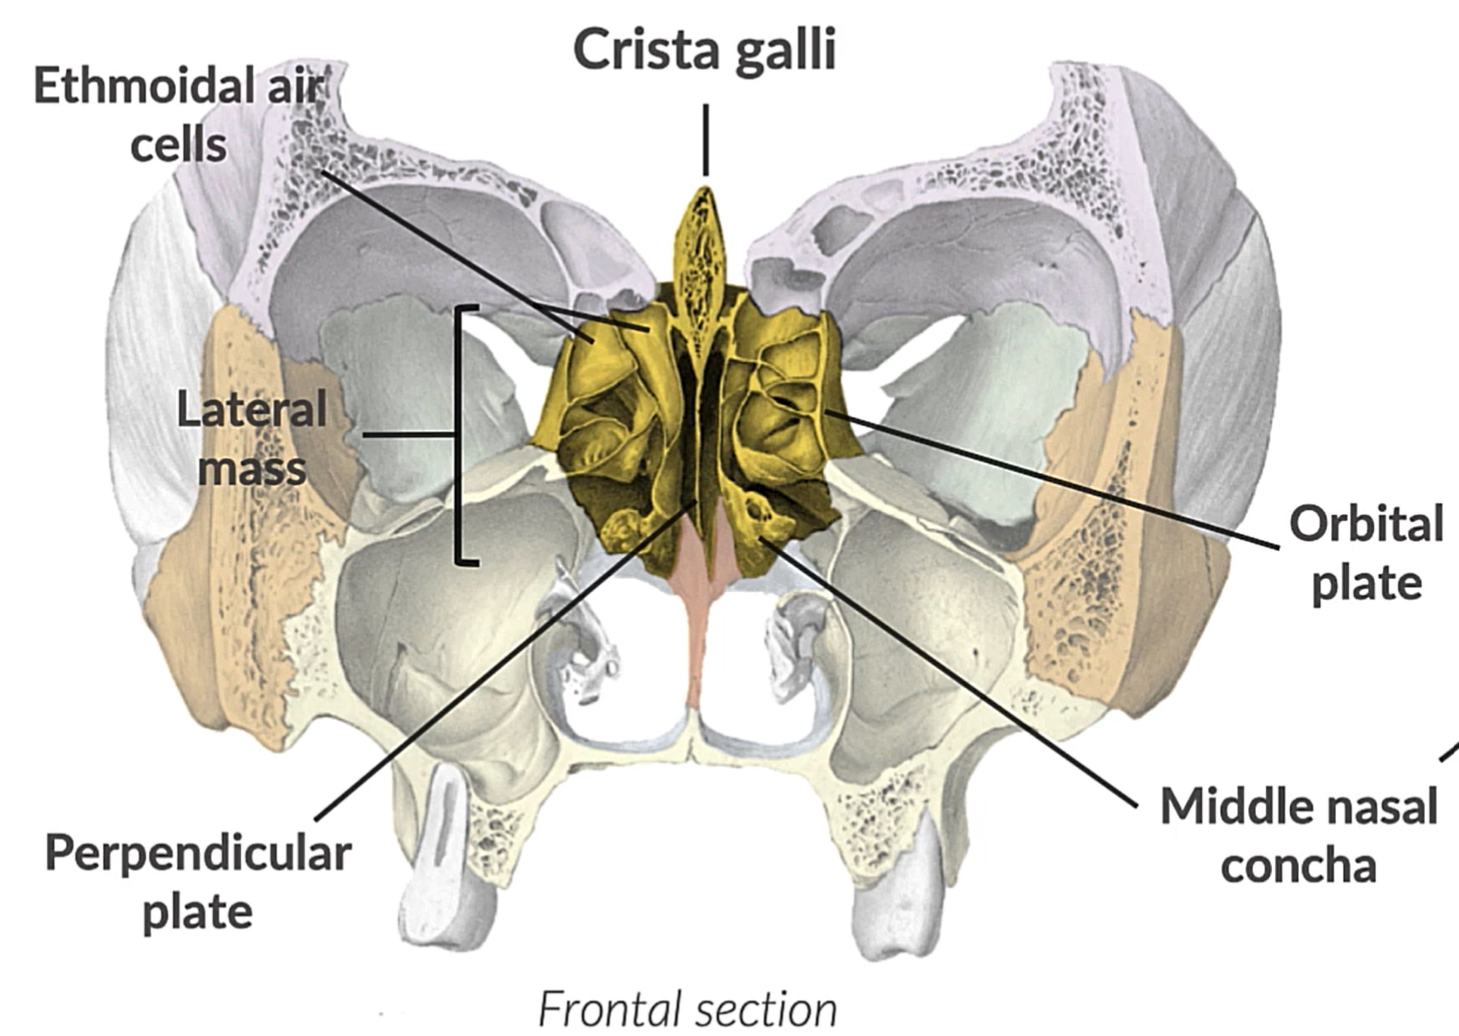

What bone is this?

Ethmoid bone

(NN)

Crista galli